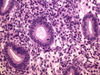

What process is occurring in this endometrium?

What process is occurring in this endometrium?